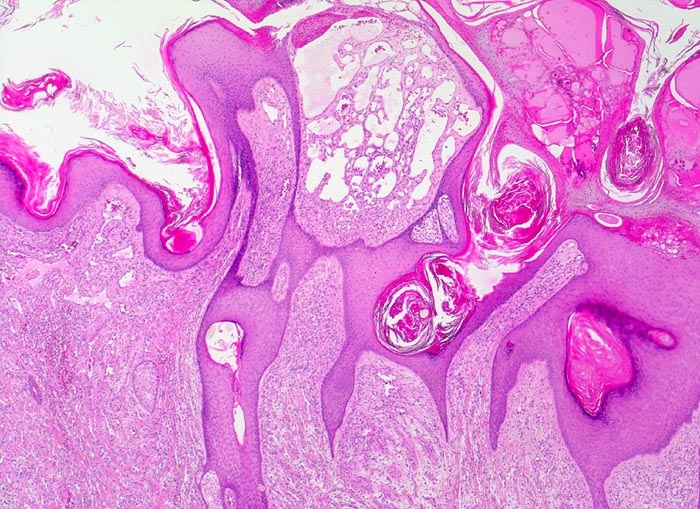

| Diagnosis: Verrucous Hemangioma Verrucous hemangioma (VH) commonly presents at birth although it may appear later in life. Lesions can be single or grouped, sometimes associated with small satellite lesions, and they occur mostly on the legs. VH starts as well-defined, macular areas of vascular staining resembling port-wine stains that with time it takes the characteristic bluish hue and a verrucous surface. Histologically, VH is characterized by a hyperplastic epidermis and the underlying dermis consisting of lobules of capillaries and vascular spaces. Clinically VH can be misdiagnosed as infantile hemangioma, angiokeratoma, and rarely as lymphangioma circumscriptum. VH is best treated by excision, but there is a tendency to recur unless excision is complete. Shahriar Nazari, Istanbul/ Turkey |